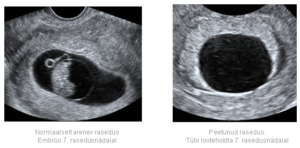

Большое яйцо также свидетельствует о неправильно развивающейся беременности. Исследования показывают, что оно развивается без эмбриона. Но в этом случае часто допускаются ошибки при ультразвуковом исследовании, поэтому лучше всего его проводить после 7 недели беременности.

Как уже упоминалось, этот диагноз звучит всегда при УЗИ обследовании. Никаким другим способом его не поставить. Врач УЗИ видит плодное яйцо с полостью, но не видит эмбрион и сердцебиение.

Как известно, при УЗИ на раннем сроке в полости плодного яйца должно быть два образования, желточный мешок и рядом с ним эмбрион. Желточный мешочек при анэмбрионии может определяться, но сам эмбрион не виден. Если УЗИ сделали очень рано, возможна ошибка, поэтому его стоит повторить через неделю или две.

После оплодотворения плодное яйцо имплантируется в стенку матки, однако эмбрион не растет или же развивается с сильной задержкой. Во время ультразвукового исследования отмечается увеличивающаяся в размерах матка, утолщающийся эндометрий и пустое плодное яйцо. Обычно его диаметр составляет около 20-25 мм.

Наличие плодного яйца является первым признаком нормально начавшейся беременности. На УЗИ-мониторе его можно увидеть через 14 дней после задержки, а эмбрион — лишь спустя пять недель.

На самых ранних сроках беременности эмбриона в плодном яйце еще не видно, и это является нормой. Однако начиная с пятой недели, он уже должен быть заметен на мониторе аппарата. Если не удается визуализировать эмбрион, то назначается повторное ультразвуковое исследование через две недели.

Если при повторном обследовании эмбриона и сердцебиения не наблюдается, то диагностируется анэмбриональная беременность. В этом случае проводится выскабливание.